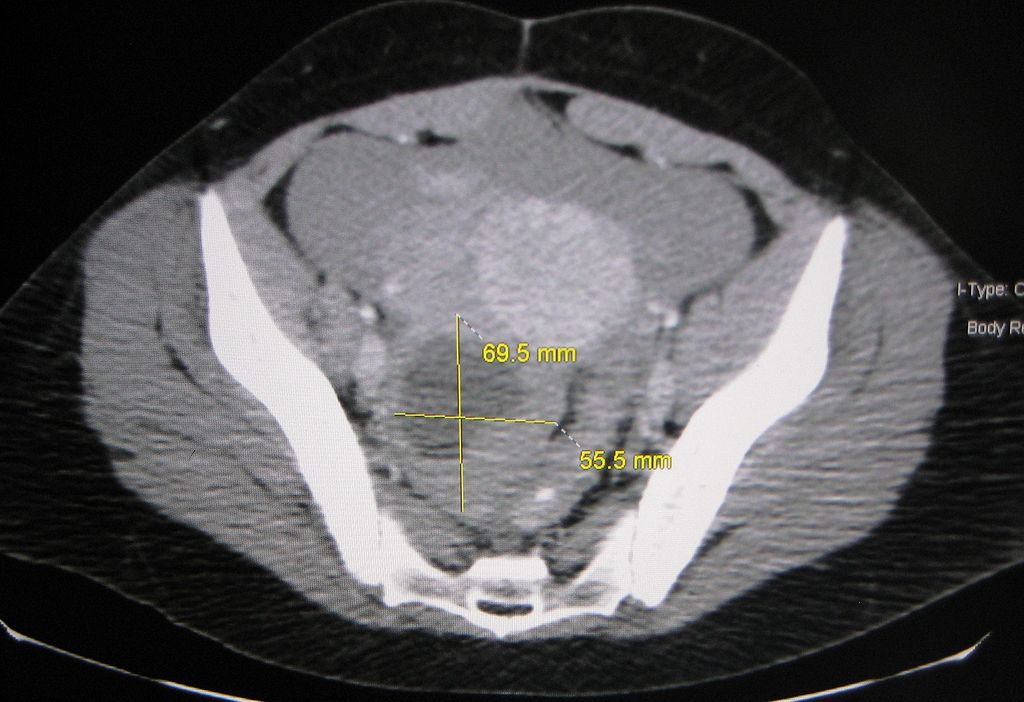

Il existe deux types de kystes bénins : Les kystes fonctionnels dus au fonctionnement de l’ovaire (ovulation) et les kystes organiques. On parle de kyste lorsque la formation qui est dépistée, le plus souvent à l’échographie, mesure plus de 3cm.

Ils peuvent parfois être hémorragiques et exceptionnellement nécessiter une chirurgie coelioscopique en urgence si le saignement est très abondant. - Les kystes organiques sont également bénins mais ne disparaissent spontanément. Il en existe plusieurs types. Ils peuvent grossir, se tordre ou exceptionnellement se rompre. Parfois l’aspect échographique permet de déterminer le type de kyste. Une IRM peut complèter le bilan mais n’est pas systématiquement nécessaire.

Ces kystes peuvent être opérés, selon les symptômes et leur taille.